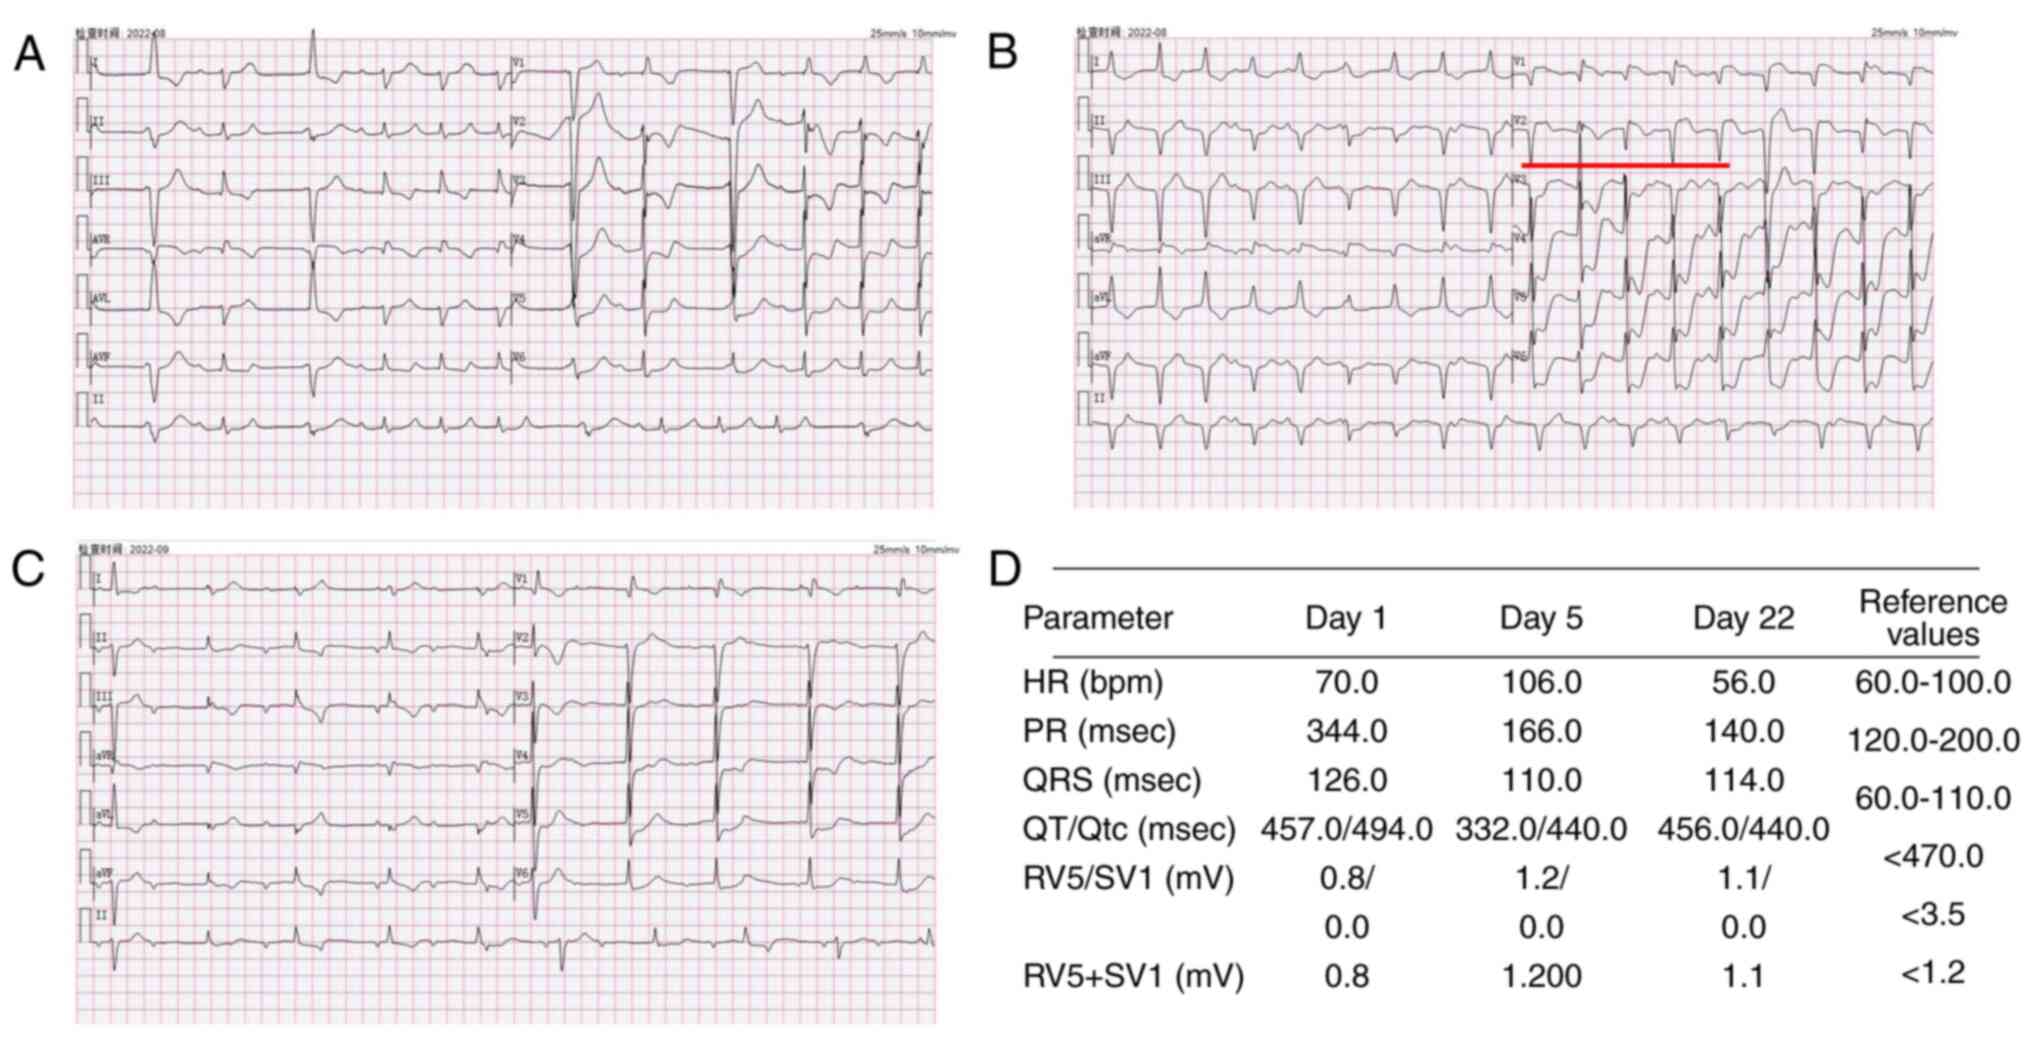

cardiac enzyme profiles. An electrocardiogram (Fig. 4) revealed sinus rhythm,

first-degree atrioventricular block, complete right bundle branch

block, frequent premature ventricular contractions and myocardial

ischemia. Acute coronary syndrome or immune-related myocarditis was

11.5 pg/ml (reference values, 0-300 pg/ml). On Day 6, paroxysmal

ventricular tachycardia was observed on monitoring. The

electrocardiogram indicated frequent ventricular premature beats

and a high risk of sudden cardiac death due to cardiac arrest

(Fig. 4B marked with red line).

| Figure 4Electrocardiograms of the patient.

Electrocardiogram performed (A) after the patient developed

palpitations (B) prior to hormonal shock therapy and (C) prior to

discharge from the hospital, the areas marked in red indicate

frequent premature ventricular contractions. (D) Parameters related

to the electrocardiograms performed and their reference ranges.HR,

Heart rate; PR, P-R interval; QRS, Total time from Q-wave, R-wave,

and S-wave on the ECG; QT, Q wave) to the end of the T wave; Qtc,

The corrected QT interval, RV5 Amplitude of the R-wave recorded on

lead V5 in the fifth intercostal space in the left anterior

axillary line; SV1, Amplitude of the S-wave recorded on the V1 lead

in the fourth intercostal space next to the right sternum. |